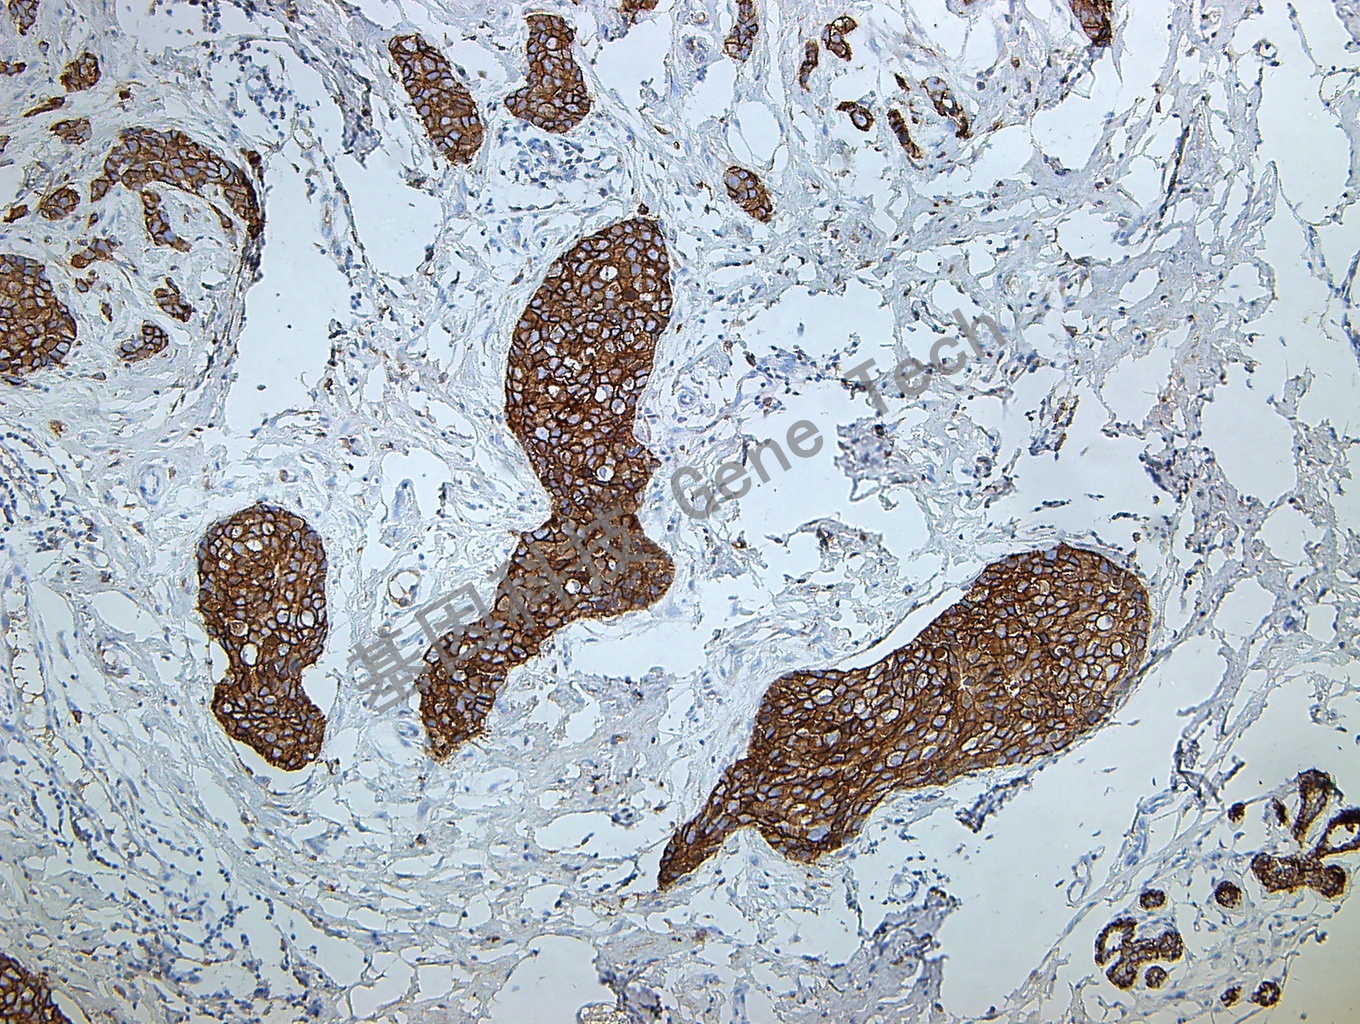

E-Cadherin 鼠抗人 E-Cadherin 抗体试剂(免疫组织化学)

| 简介:E-cadherin是跨膜糖蛋白,属于上皮细胞钙离子依赖的粘附分子家族,在组织的生长发育中发挥重要作用,其功能的降低/ 丧失可导致细胞连接的破坏,与肿瘤细胞的浸润和转移相关。其表达与肿瘤分化程度成反比。表达的缺失与许多癌的进展相关,包括乳腺癌、膀胱癌和头颈部鳞癌,也同肝细胞癌高级别相关。尽管此抗体上皮样肉瘤中不表达,但是若在肉瘤中表达可能同上皮样分化相关。在渗出液中区别非肿瘤性间皮细胞和癌细胞(在渗出液中的卵巢肿瘤细胞E-cadherin 高表达);在鉴别间皮瘤和其他缺少细胞粘附力的肿瘤(如:乳腺小叶癌和胃癌,这些肿瘤有着很高频率的突变。)中有一些价值;现在也有报道可用于乳腺小叶癌和导管癌的鉴别(后者常为阳性,前者常阴性)。 | ||

| 乳腺癌石蜡切片,用 E-Cadherin(GT2348)染色,细胞膜阳性,DAB 显色。 | ||